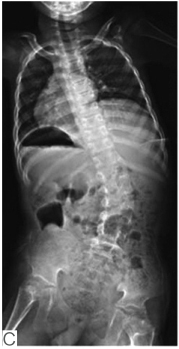

有研究报道,约20%~67%的先天性多发性关节挛缩症患者可出现脊柱侧凸。这类患者往往出生时就表现为脊柱畸形,反映出胎儿在母体宫内位置(图4)。在婴儿期脊柱侧凸进展很快,直至儿童后期才趋于稳定。大多数脊柱侧凸在5岁前可发现,对于肌发育不良及综合征型关节挛缩患者来说,胸弯及胸腰弯更多见,腰弯少见。对远端关节挛缩患者来说,胸腰弯更多见,此类患者侧凸进展比其他类型更快(图5)。

图4肌发育不良新生儿临床特征表现

A.显示明显脊柱侧凸,反应宫内胎位情况;B.同一小孩4岁时行平卧位X线提示腰段30°侧凸;C.同一小孩9岁时行平卧位X线提示腰段42°侧凸(引自Komolkin I, et al. Treatment of Scoliosis Associated With Arthrogryposis Multiplex Congenita.J Pediatr Orthop,2017, 37 Suppl 1:S24-S26.)